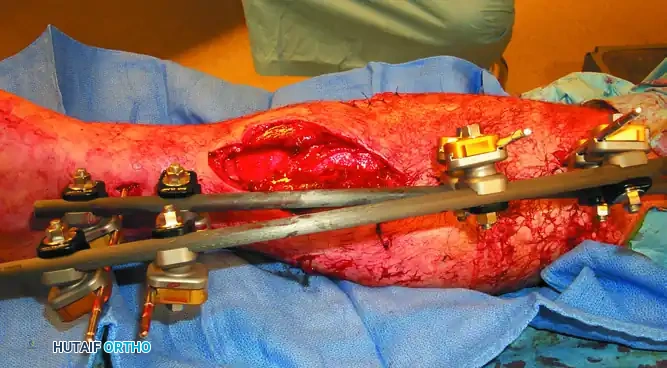

Step-by-Step Surgical Technique

2. Pin Insertion Technique

- Incision: Make a longitudinal stab incision (1-2 cm) through the skin. Do not use a puncture technique, as skin tension around the pin leads to necrosis and infection.

- Blunt Dissection: Use a hemostat to bluntly dissect down to the periosteum. Insert a tissue protection sleeve (drill guide) firmly against the bone.

- Pre-drilling: Always pre-drill the near and far cortices using a sharp drill bit. Use continuous saline irrigation to cool the drill bit. Thermal necrosis from drilling is the primary cause of premature pin loosening and ring sequestrum formation.

- Pin Placement: Insert the half-pin manually or on low speed. Ensure the pin engages the far cortex but does not protrude more than 1-2 threads to avoid tethering far-side soft tissues.

3. Frame Assembly and Reduction

- Apply the pin-to-bar clamps to the pins.

- Attach the longitudinal carbon fiber or titanium rods.

- Perform the fracture reduction under fluoroscopic guidance using manual traction.

- Once length, alignment, and rotation are restored, sequentially tighten all clamps.

- Verify the final reduction and ensure the frame is 2-3 cm away from the skin to accommodate swelling.